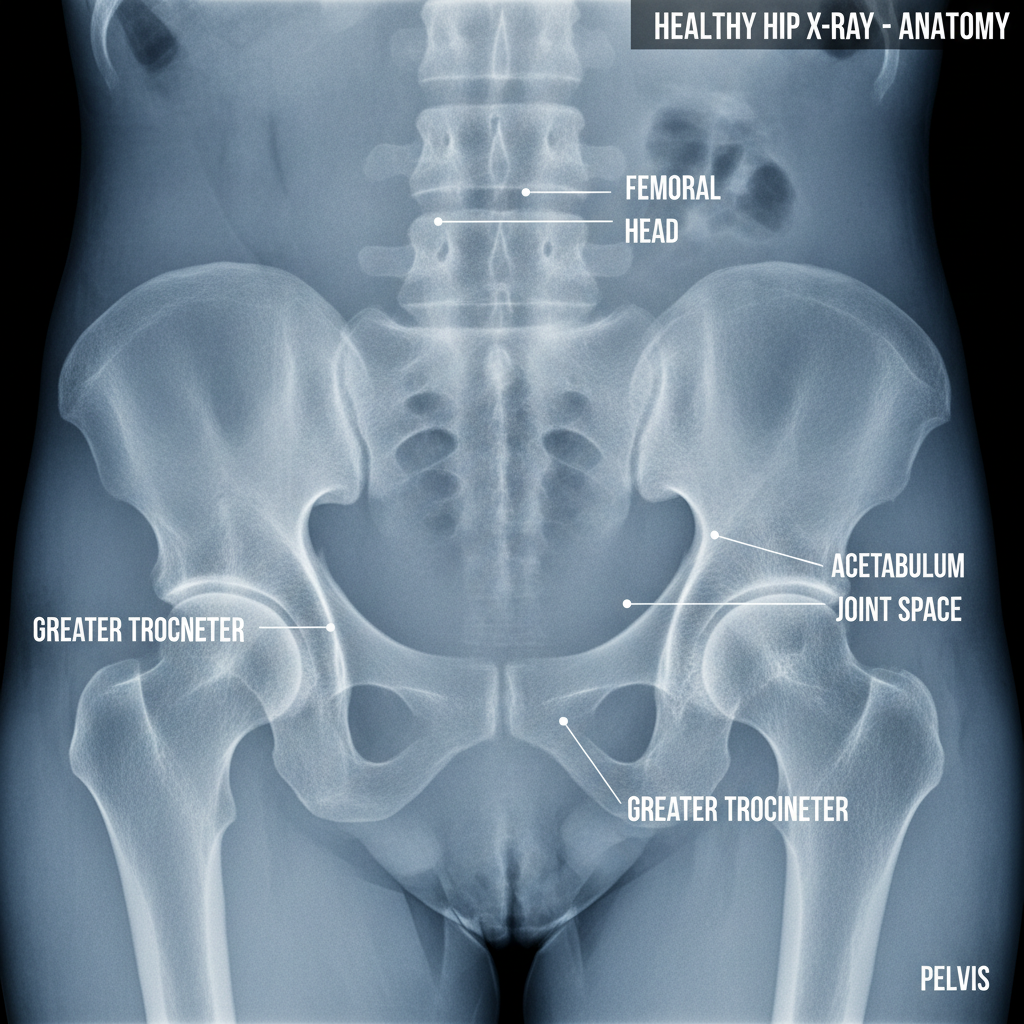

Anatomia: jak działa zdrowy staw biodrowy

Staw biodrowy to mistrz inżynierii ewolucyjnej: kulista głowa kości udowej osadzona jest w panewce miednicy, otoczonej silną torebką stawową i licznymi więzadłami. Ten układ zapewnia stabilność oraz imponujący zakres ruchu – od siedzenia przez bieganie po taniec. Prawidłowa głębokość i nachylenie panewki sprawiają, że głowa kości udowej nie „wyskakuje” ze stawu, nawet podczas dynamicznych ruchów (Medikar, 2023). Każda deformacja tego systemu – spłycenie, zniekształcenie, niewłaściwy kąt nachylenia – zwiększa ryzyko destabilizacji. Stąd znaczenie precyzyjnej diagnostyki obrazowej już od pierwszych tygodni życia dziecka.

Zdjęcie RTG stawu biodrowego zdrowej osoby; słowa kluczowe: anatomia biodra, zdrowy staw biodrowy, zdjęcie rentgenowskie

Na poziomie mikroskopowym staw biodrowy to nie tylko kości, ale też chrząstka szklista, błona maziowa i system amortyzujący wstrząsy. U noworodków struktury te są jeszcze niedojrzałe – panewka bardziej chrzęstna niż kostna, a więzadła rozciągliwe. To właśnie ten moment rozwojowy decyduje, czy wszystko „ułoży się” prawidłowo, czy pojawią się pierwsze zaburzenia.